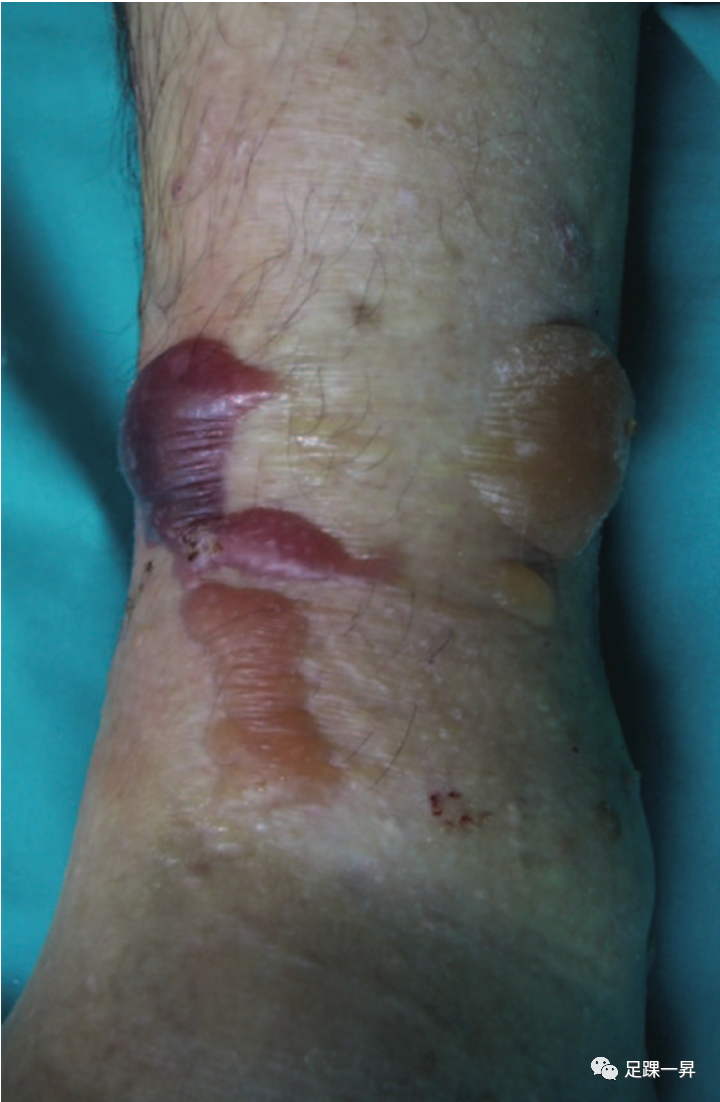

△图示高能量Pilon骨折患者系列一,通常伴有严重的软组织损伤,表现为明显的肿胀和骨折张力性水泡。

△图示高能量Pilon骨折患者系列二,通常伴有严重的软组织损伤,表现为明显的肿胀和骨折张力性水泡。

△图示高能量Pilon骨折患者系列三,通常伴有严重的软组织损伤,表现为明显的肿胀和骨折张力性水泡。

△图示高能量Pilon骨折患者系列四,通常伴有严重的软组织损伤,表现为明显的肿胀和骨折张力性水泡。

△图示高能量Pilon骨折患者系列五,通常伴有严重的软组织损伤,表现为明显的肿胀和骨折张力性水泡。